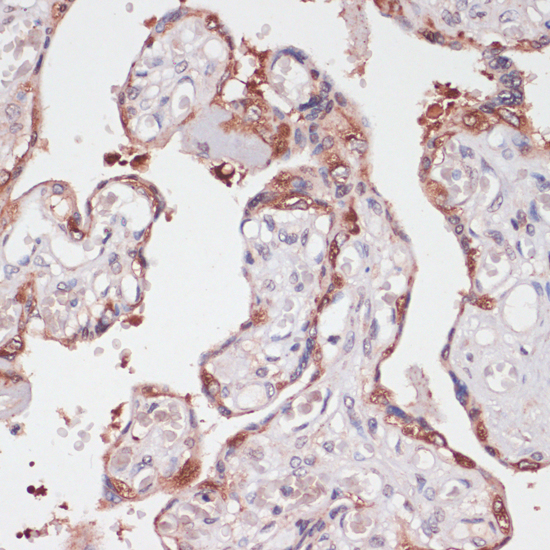

Immunohistochemistry of paraffin-embedded human placenta using TPD52 at dilution of 1:100 (40x lens).